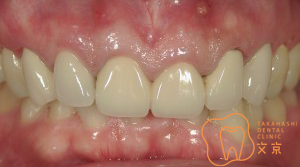

■前歯を治したい。 オールセラミックスによる審美治療

■前歯を治したい。40代男性 オールセラミックスによる審美治療

■前歯を治したい 精密審美治療・セラミックス治療

■前歯 精密審美治療

■前歯のセラミックス治療 審美治療

■前歯のオールセラミックス治療

■保険の前歯を直したい